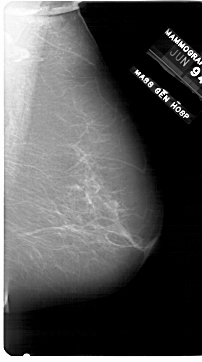

A_1750_1.LEFT_MLO

LEFT_MLO LINES 6871 PIXELS_PER_LINE 3781 BITS_PER_PIXEL 12 RESOLUTION 43.5 OVERLAY

FILE: A_1750_1.LEFT_MLO.OVERLAY

TOTAL_ABNORMALITIES 1

ABNORMALITY 1

LESION_TYPE MASS SHAPE ROUND MARGINS CIRCUMSCRIBED

ASSESSMENT 3

SUBTLETY 4

PATHOLOGY BENIGN

TOTAL_OUTLINES 1

BOUNDARY